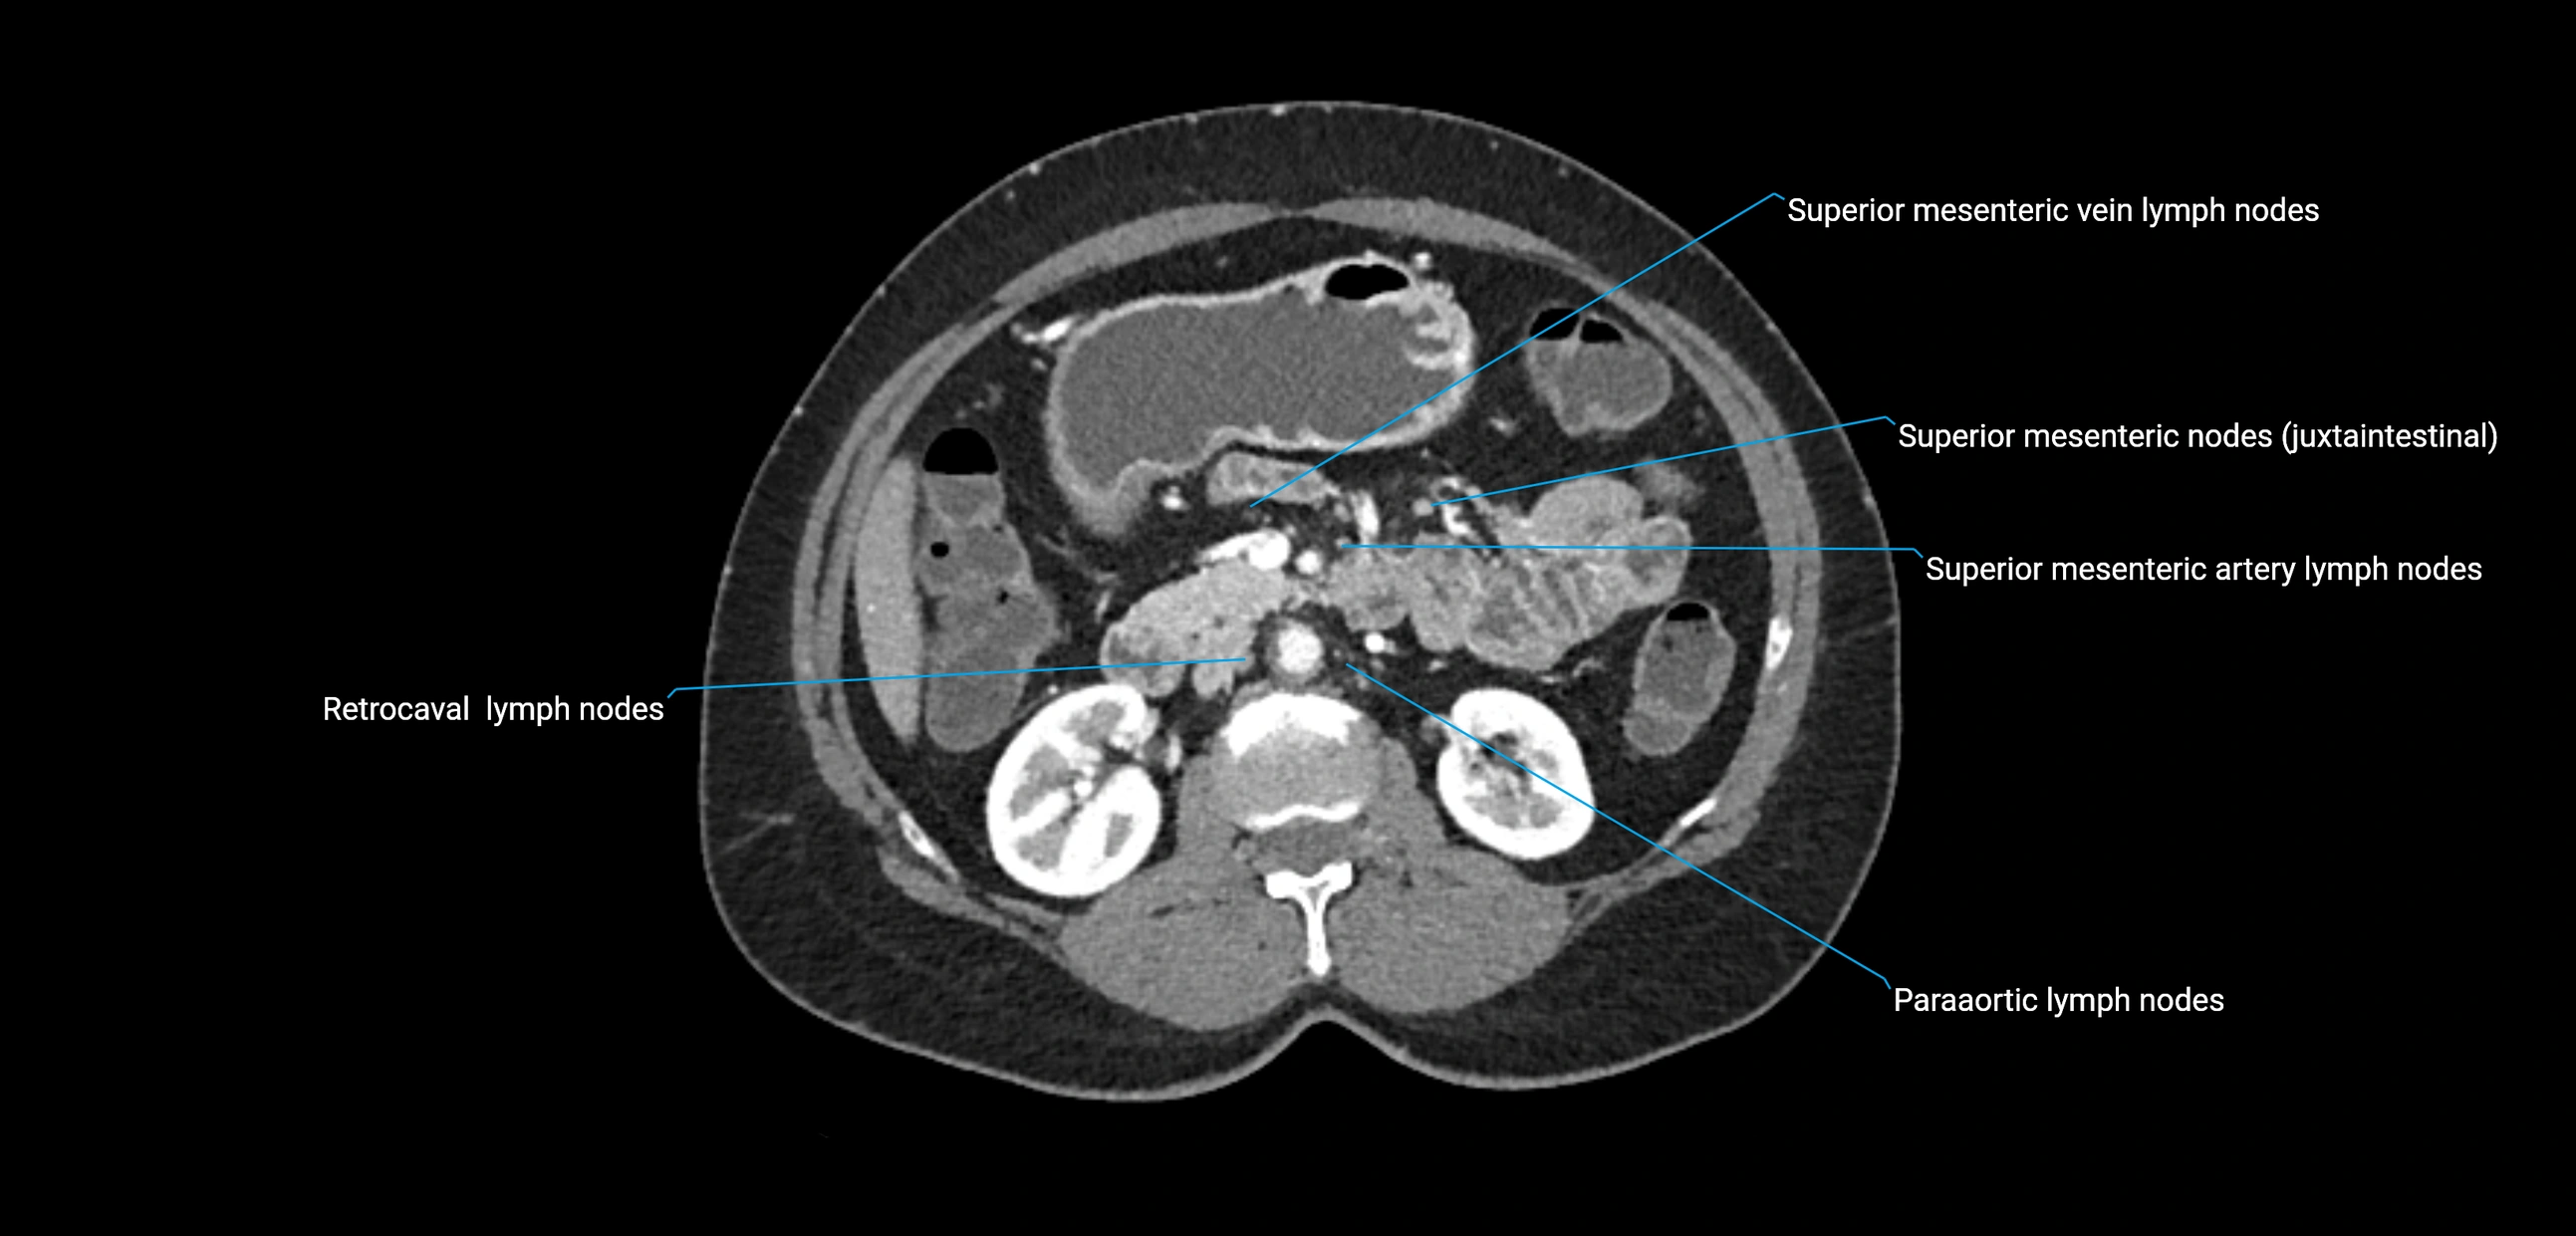

CT Appearance

CT Pre-Contrast:

• Nodes appear as soft-tissue density nodules adjacent to the aorta and IVC

• Calcification may be seen in chronic infections (e.g., tuberculosis)

CT Post-Contrast:

• Normal nodes enhance homogeneously

• Malignant nodes may show heterogeneous enhancement, central necrosis, or conglomerate formation

• Size >1 cm short axis is suspicious, though morphology and distribution are equally important

CT Venography (CTV):

• Demonstrates nodal encasement or compression of adjacent vessels (aorta, IVC, renal veins)

• Useful in staging testicular and ovarian malignancies

• Provides 3D reconstructions for retroperitoneal lymph node dissection planning

CT image

image